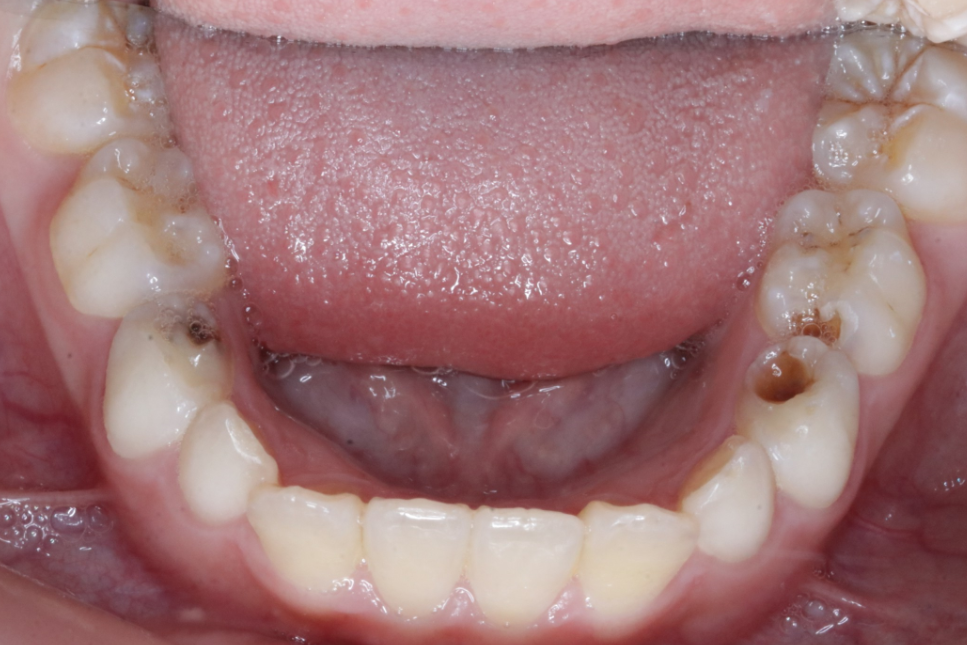

“起死回生”技术

“牙髓再生”技术是我科室率先在资阳市开展的生物组织学工程技术,利用自体血液促进仿牙髓组织再次发育,促进年轻恒牙牙根继续发育直至发育完成。相比传统技术,可以有效增加牙根的长度,粗度。

根尖炎症导致牙根停止发育

经过牙髓再生技术后,6个月后,根尖炎症消失,牙根长度增加,牙根的厚度增加